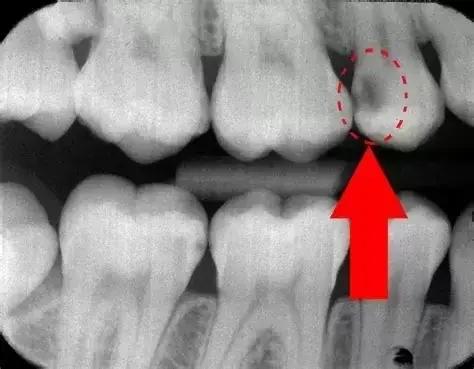

- عکس بیندندانی (برای تشخیص پوسیدگیهای مخفی)؛ این عکس مخصوص بررسی فواصل بین دندانهاست؛ نقاطی که با چشم غیرمسلح قابل مشاهده نیستند. در این تصاویر، پوسیدگیها به صورت لکههای تیره و غیرطبیعی بین دندانها نمایان میشوند.

برای تفسیر عکس دندان، ابتدا به رنگها دقت کنید. بخشهای سفید روشن نشاندهندهٔ ساختارهای سخت مانند مینای دندان، پرکردگیهای فلزی یا استخوان فک هستند؛ در حالیکه نواحی خاکستری یا تیرهتر، بیانگر بافتهای نرمتر مانند عاج یا لثهاند. اگر قسمتهایی تاریک و نامنظم بین یا درون دندانها مشاهده شود، احتمالاً نشانهٔ پوسیدگی یا حفرههای دندانی است.

- لکههای تیرهای که بین دندانها دیده میشوند، معمولاً نشانهٔ پوسیدگی یا مشکلات احتمالی هستند و باید با دقت بررسی شوند.